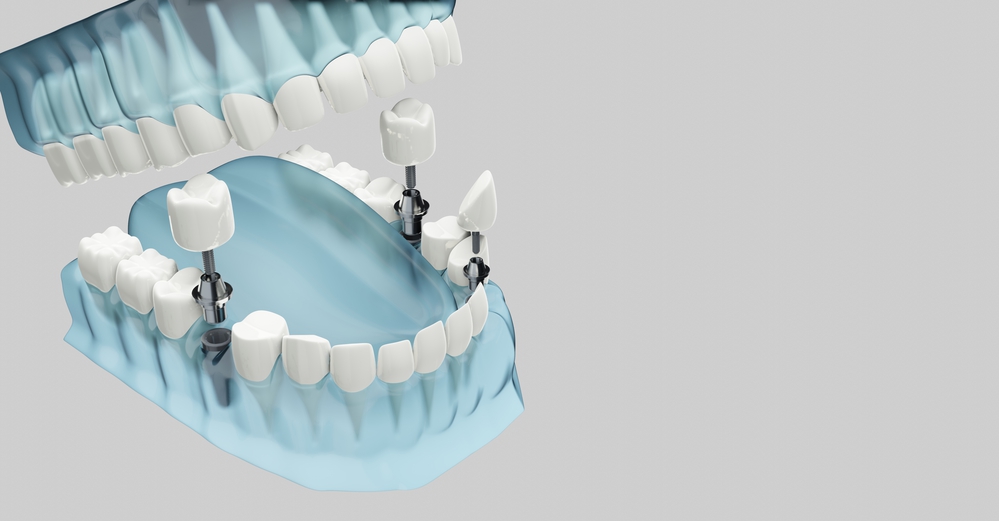

When considering options for replacing missing teeth, implant-supported dentures represent a significant advancement in dental technology. Away from traditional dentures, which rest on the gums, implant-supported dentures are attached to dental implants surgically positioned in the jawbone. This method offers enhanced stability, preventing the slipping or shifting often occurring with regular dentures. Additionally, these dentures can help maintain jawbone health, as the implants act like tooth roots, stimulating the bone. Patients interested in this option should inquire about the procedure’s suitability for their specific dental condition, the expected longevity of the implants, and the care regimen to ensure lasting results.

Understanding the expected lifespan and durability of implant-supported dentures is crucial for making informed decisions about your dental care. These dentures are designed to be a long-term solution for tooth replacement. On average, they can last 10 to 20 years or even more with proper care. The durability of implant-supported dentures results from their stable foundation, which consists of dental implants securely anchored in your jawbone. This foundation ensures that your dentures are durable, functional, and capable of withstanding the demands of daily use. Discussing the expected lifespan and durability with your New York City dentist allows you to plan for long-term dental maintenance and maximize your investment in oral health.

The process typically begins with a consultation with your dentist, where you discuss your goals and assess your eligibility. Subsequent steps may include dental implant placement, healing, osseointegration (the process of implants fusing with your jawbone), and the final attachment of your dentures. The timeline for this process can vary depending on individual factors, such as the need for additional treatments or the healing rate of your jawbone. Your New York City dentist will provide a detailed outline of the procedure steps and an estimated timeline based on your specific case, allowing you to prepare accordingly.